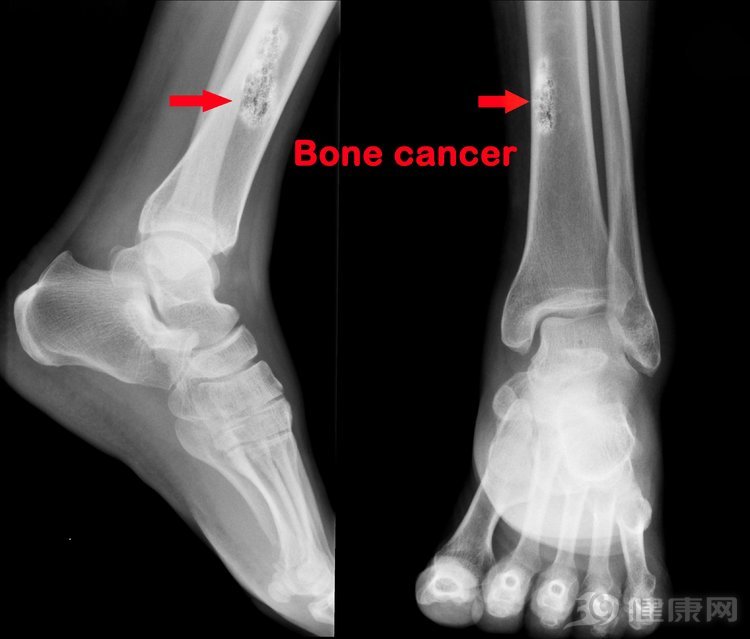

骨肉瘤,恶性肿瘤的一种,通常在长骨部位发生,比如胳膊或者腿,骨盆、脊柱、下颚等也可能出现。骨肉瘤发病率在癌症当中是比较低的,大约在百万分之三,但是骨肉瘤治疗难度大,因为骨肉瘤病因目前还不明确,早期的时候症状也多是比较隐匿的,很容易被忽视,像上述提到的王思蓉就是被耽误的,所以还是要引起高度重视。

骨肉瘤最喜欢祸害青少年,因为这个时期骨生长速率最快,但是骨肉瘤的痛常常会被当做生长痛,从而导致患者被延误治疗,所以大家一定要注意:“生长痛”多是运动后疼痛,与肌腱的止点相关,比如压迫胫骨结节止点或者鹅足时,患者会有疼痛加重的感觉,而骨肉瘤的疼痛多为持续性疼痛,不动时也会感到疼痛,尤其在患者睡着之后会更加明显。

所以,一旦遇到孩子有夜间痛、关节屈曲畸形等现象,一定要警惕骨肉瘤,并做相关的检查与治疗。